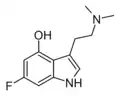

| 6-Fluoropsilocin | artificial | 4-OH,6-F | CH3 | CH3 | 4-hydroxy-6-fluoro-N,N-dimethyltryptamine | 312314-12-8 |